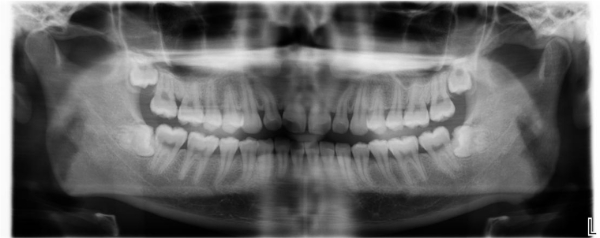

治療前,環口X光,深度蛀牙